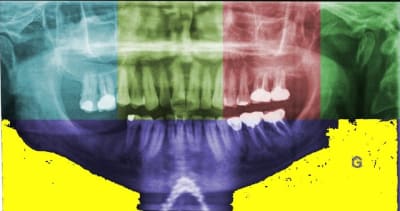

> Bon, tirés de ma collection perso quelques petites

> panos avec des cas où vous pourrez vous en donner

> à coeur joie sur savoir ce qu'il faut faire (les

> deux patients sont un chauffeur de bus et l'autre

> retraité de la mairie)

Je trouve que l'idée d'Annie est bonne. Pas pour prouver que les implants, ça marche, mais pour nous faire plaisir en voyant des réhabilitations après quelques années .Car, ce qu'il y a de mieux que sur Pub Med ici, c'est que l'on peut y voir des images.

> des images.

l'inconvénient c'est qu'on ne peut pas les colorier.

Pas d'accord !

joli,Marc,Appap,mais la couleur n'était pas nécessaire